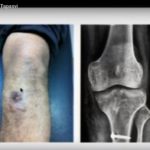

Courtesy: Sachin Tapasvi, David Rajan, Arthroscopy Course